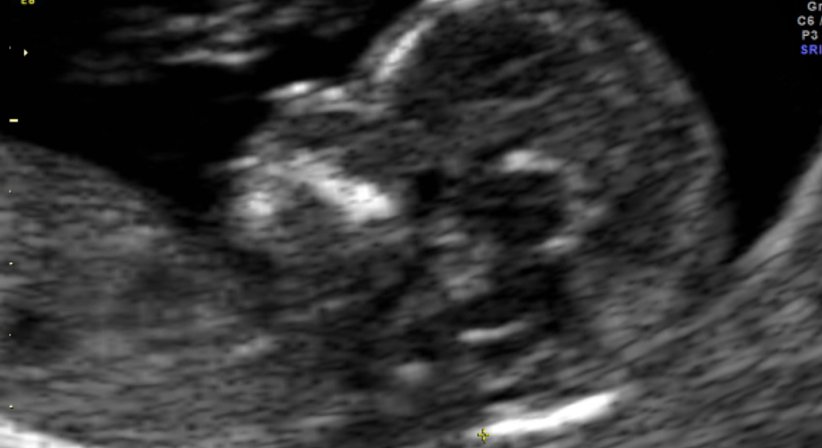

Zwischen der 12. (11 + 0) und der 14. Schwangerschaftswoche (13 + 6) ist es möglich das sogenannte Ersttrimesterscreening inkl. Nackentransparenzmessung (Nackenfaltenmessung), durchzuführen. Hierbei wird Ihr Baby das erste Mal von „Kopf bis Fuß"genau untersucht. Grobe Auffälligkeiten können so schon sehr früh ausgeschlossen werden.

Zudem kann eine Risikoeinschätzung bezüglich schwerer genetischer Störungen (Down Syndrom, Trisomien) getroffen werden.